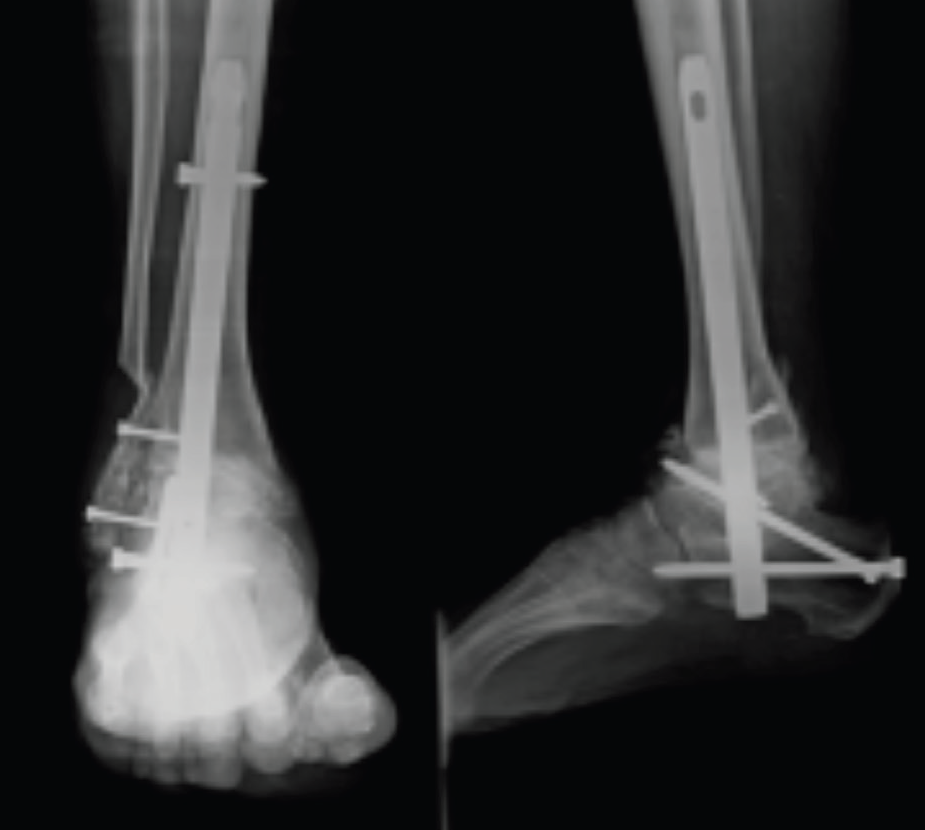

Eklemlerin Dondurulması (Artrodez): Hareket kaybının çok önemli olmadığı bazı eklemlerde (örneğin ayak bileği ve elin küçük eklemleri) uygulanır. Aşınmış olan eklem yüzleri çıkartılır ve iki kemiğin birbirine kaynaması sağlanır. Ağrı tamamen geçer ancak eklemde hareket olmaz.

|